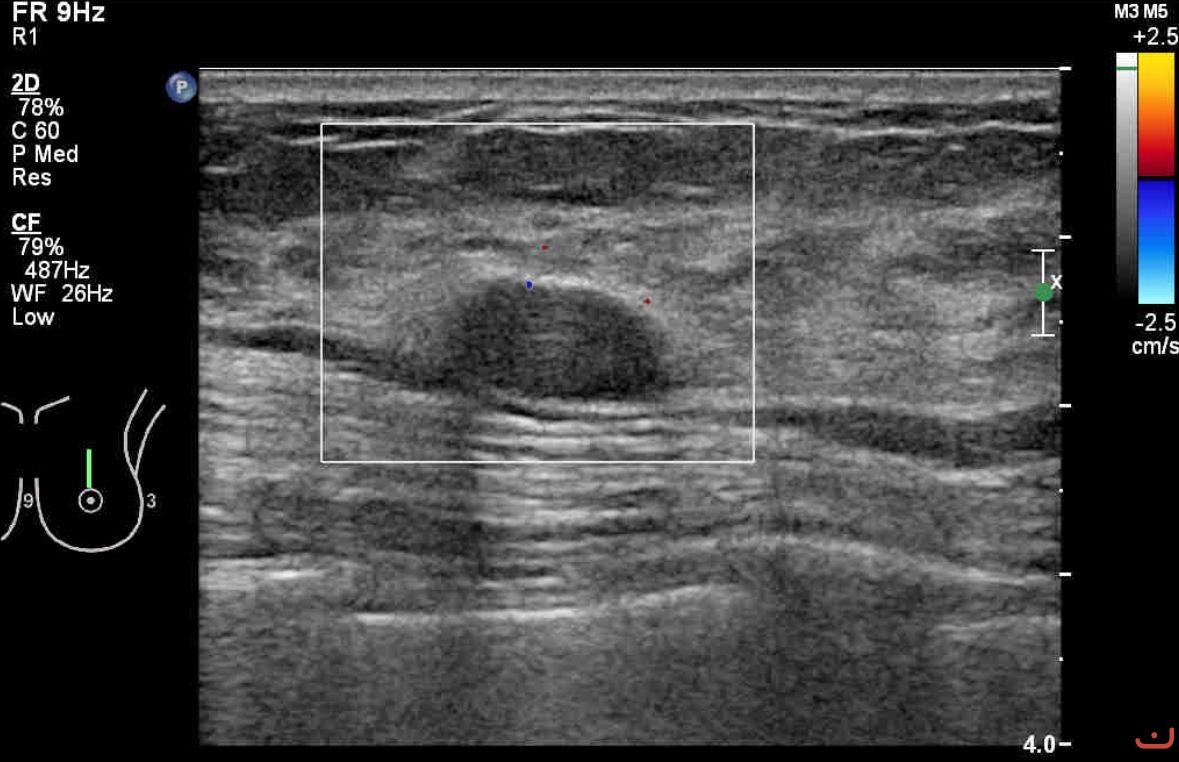

Benign solid mass

Sunday, 16 August 2015

118.10 KB (1179 x 762 px)